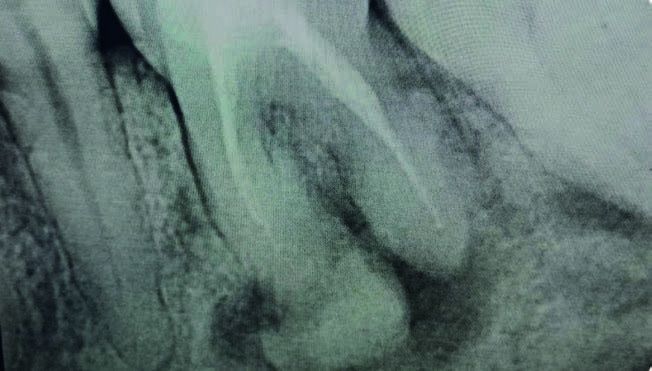

En noviembre de 2024, la paciente acudió a consulta presentando una fractura vertical en el molar 36, lo que requirió su exodoncia. A nivel radiográfico (Figura 4), se observó un aumento significativo de material radiodenso en la zona, particularmente en la región de la raíz mesial.